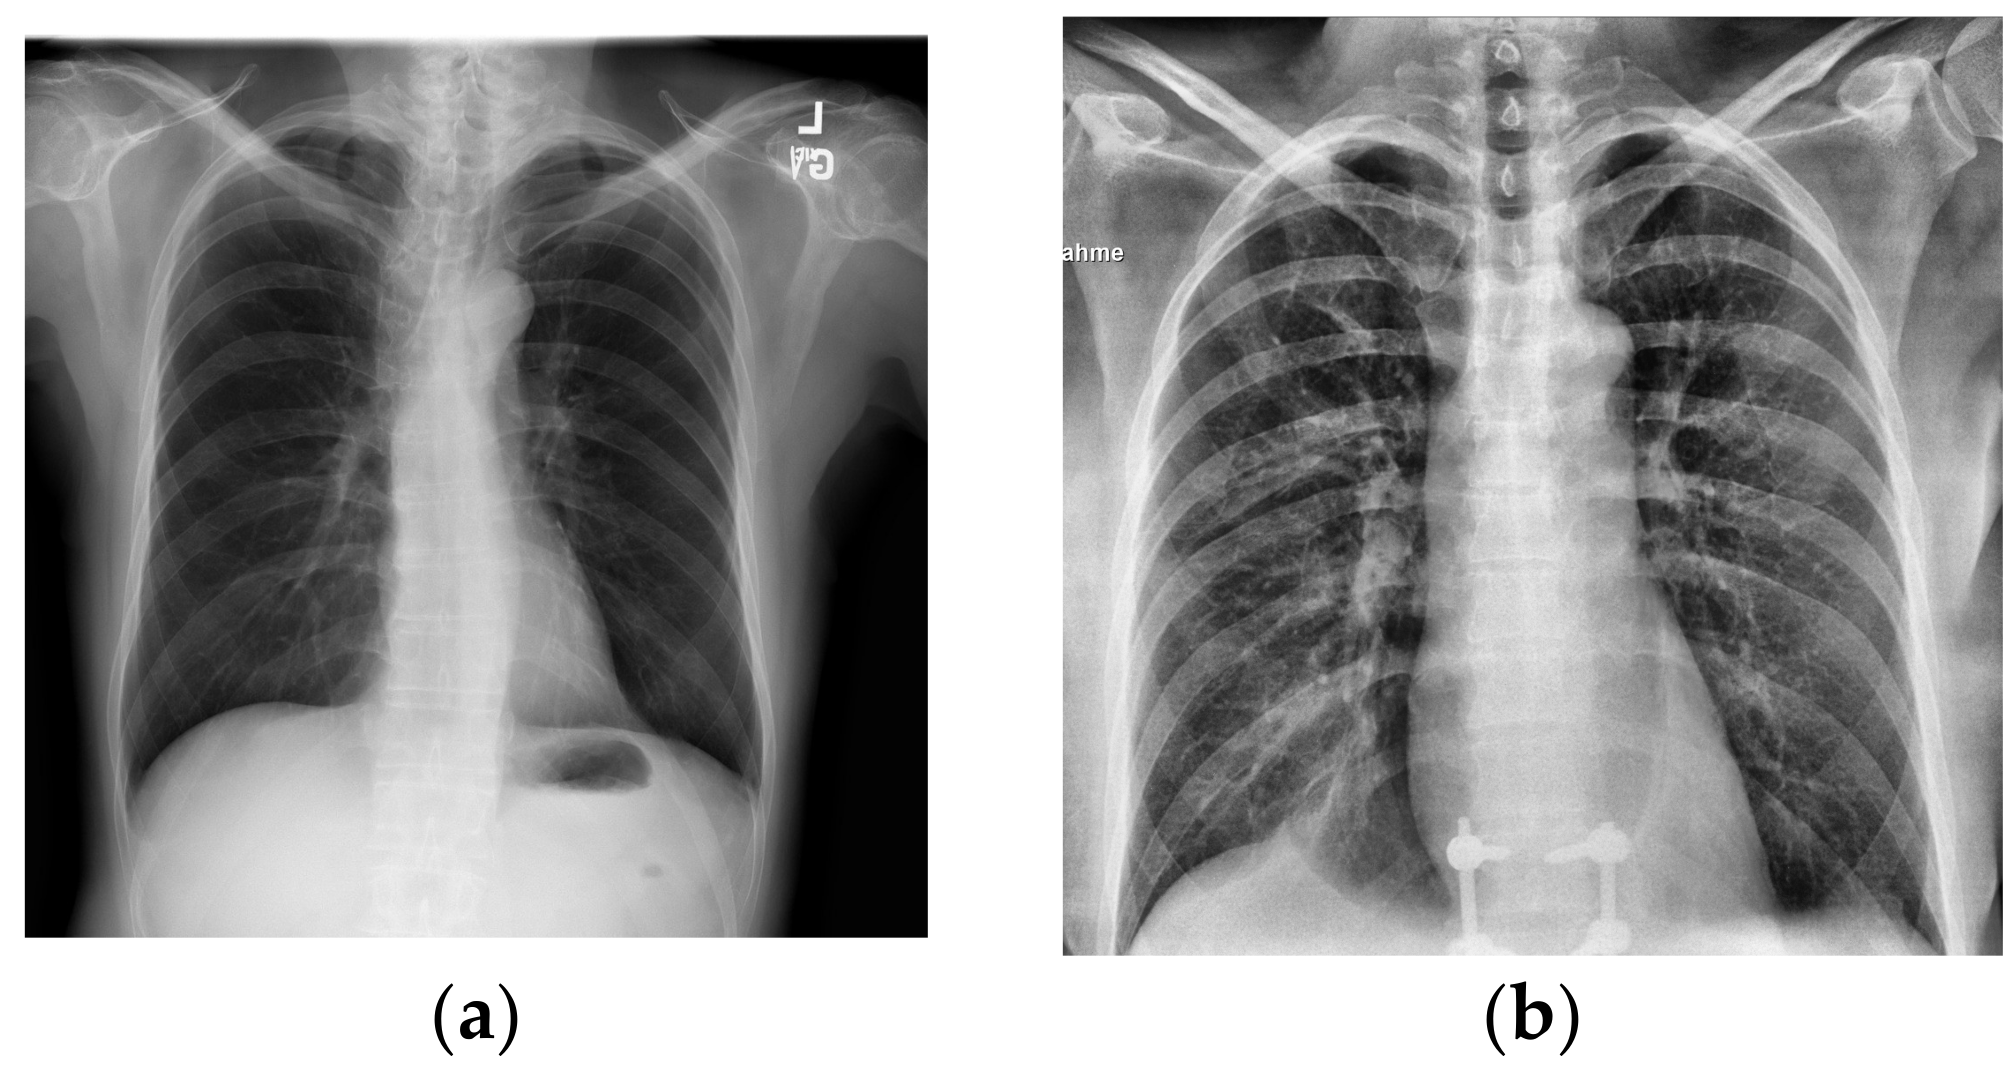

Although in Figure 1a,b the differences in lung health are obvious, with large white opacities in the infected lung, the differences between healthy lungs and lungs infected by COVID-19 are often much more subtle. Additionally, some other illnesses like pneumonia can appear similar in an X-ray to COVID-19, requiring intensive review to distinguish them from the latter virus. With cases drastically increasing each day, it can take a significant amount of time for doctors to analyze these X-rays that could be used for treating patients instead. Couple this with the tedious work of manually analyzing hundreds of images in a high stress environment and there is an even greater overburdening of doctors and risk of mistakes.

Figure 1.

X-rays of healthy and infected patients. X-rays from [7,8]. (a) Sample X-ray for healthy lungs. (b) Sample X-ray for COVID-19-infected lungs.